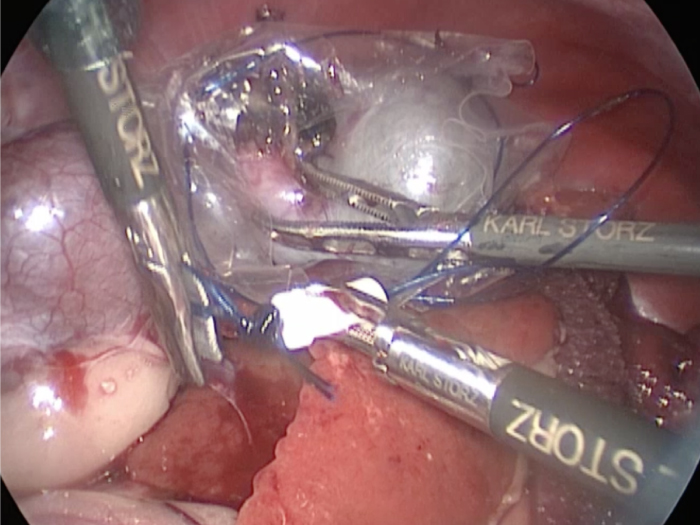

体の外に出すためお腹の中で袋に入れていきます。

このときに胆嚢と一緒にクリップやガーゼも回収します。

そしてお腹の中をきれいにしていきます。

最後にお腹の中をきれいに洗浄していきます。

回収袋にいれて体外に摘出していきます。

お腹の中を洗浄して終了となります。